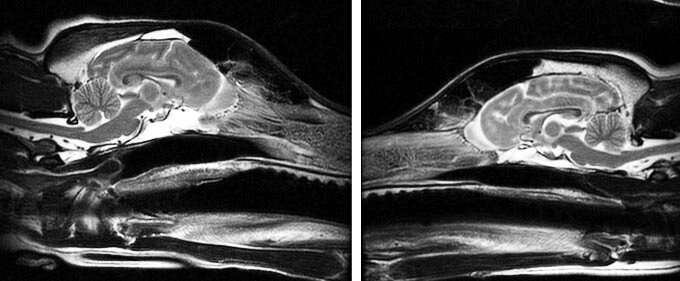

Исследование мозга 62 чистокровных собак, представляющих 33 породы, показывает, что мозг собаки не все одинаковы — предлагая отправную точку для понимания того, как анатомия мозга относится к поведению. У разных пород были разные формы различных областей мозга, различия, которые не были просто результатом формы головы или размера мозга или тела собак.

МРТ-снимки были взяты у собак с нормальной анатомией мозга в ветеринарной клинике. Хотя исследование не было разработано для прямой связи формы мозга с поведением, результаты дают некоторые подсказки. Исследователи выделили группы областей мозга, таких как области запаха и вкуса, которые показали наибольшую вариабельность между породами. Эти группы вовлечены в специализированные формы поведения, которые часто служат людям, такие как охота по запаху, охрана и обеспечение общения с людьми, как предполагали более ранние исследования.